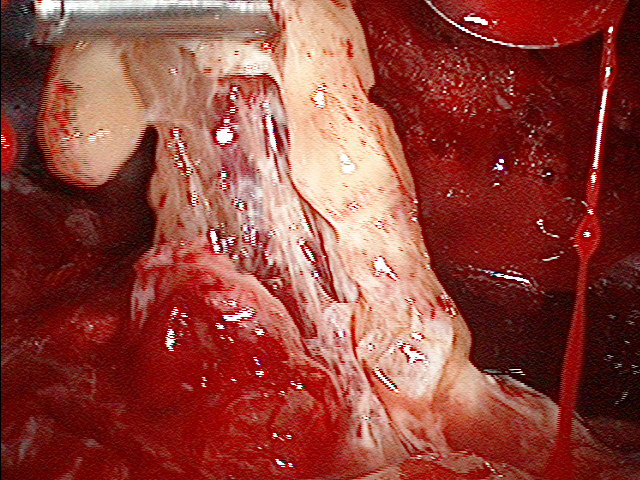

Absceso pleural apical posterior